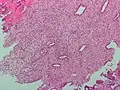

![]() Endometrium in the proliferative phase | |

The endometrium consists of a single layer of columnar epithelium plus the stroma on which it rests. The stroma is a layer of connective tissue that varies in thickness according to hormonal influences. In the uterus, simple tubular glands reach from the endometrial surface through to the base of the stroma, which also carries a rich blood supply provided by the spiral arteries. In women of reproductive age, two layers of endometrium can be distinguished. These two layers occur only in the endometrium lining the cavity of the uterus, and not in the lining of the fallopian tubes.[4][5]

It is possible to identify the phase of the menstrual cycle by reference to either the ovarian cycle or the uterine cycle by observing microscopic differences at each phase—for example in the ovarian cycle:

| Phase | Days | Thickness | Epithelium |

| Menstrual phase | 1–5 | Thin | Absent |

| Follicular phase | 5–14 | Intermediate | Columnar |

| Luteal phase | 15–27 | Thick | Columnar. Also visible are arcuate vessels of uterus |

| Ischemic phase | 27–28 | Columnar. Also visible are arcuate vessels of uterus |